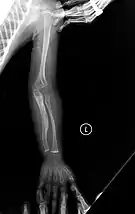

- Type V – Having the same clinical features as type IV, it can be clinically distinguished by observing a "mesh-like" appearance to a bone biopsy under a microscope. Type V can be further distinguished from other types of OI by the "V triad": an opaque band (visible on X-ray) adjacent to the growth plates; hypertrophic calluses (abnormally large masses of bony repair tissue) which form at fracture sites during the healing process; and calcification of the interosseous membrane of the forearm,[50] which may make it difficult to turn the wrist.[1]: 429 Other features of this condition may include pulled elbow, and, as in other types of OI, long bone bowing and hearing loss.[64] Cases of this type are caused by mutations in the IFITM5 gene on chromosome 11p15.5.[64][49] The separation of type V from type IV OI, its clinical type, was initially suggested even before its genetic cause was known, by Glorieux et al. in 2000.[50][65] Type V is relatively common compared to other genetically defined types of OI—4% of OI patients at the genetics department of the Brazilian Hospital de Clínicas de Porto Alegre were found to have it.[66]